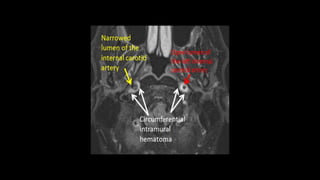

• #162 Here is an example of a young patient presenting with severe acute neck pain SHOWING left ICA dissection ON T2wi AS crescentric shaped hyperintense intramural hematoma causing expansion of the artery. However there is no narrowing of ICA lumen

• #163 Another example showing circumferential intramural hematoma seen bilaterally causing expansion of the bilateral ICA . There is narrowed lumen of the right ICA and open lumen of the left ICA